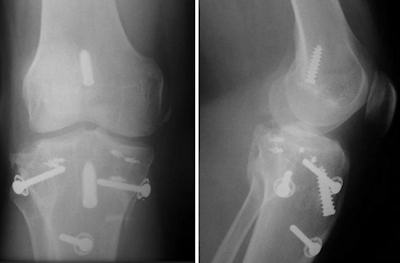

- KD V: Kırıklı çıkık

Doku hasarı tamire izin vermeyecek kadar fazla ise yan bağlara da primer tamir yerine rekonstrüksiyon yapılabilir (Stannard JP, Am J Sports Med 2005). Çapraz bağların kemik avülziyonları primer tespit edilebilir. Twaddle’ın serisinde tamir edilebilir avülziyonlar en sık dış yan bağ ve arka çapraz bağda saptanmıştır (J Orthop Trauma 2003.). Ancak bağın gövdesinden olan yaralanmalarda allogreft rekonstrüksiyon tercih edilmelidir.

Özellikle arka çapraz bağ için yeterli sağlamlıkta greft kullanılmalıdır. Hem ön hem de arka çapraz bağın birlikte yaralandığı durumlarda tek demet rekonstrüksiyonlar tercih edilmelidir. İki demet rekonstrüksiyon yapılacaksa, sürenin uzayacağı ve morbiditenin artacağı da göz önüne alınarak sadece arka çapraz bağ için uygulanmalıdır. Tibial rim kırıklarının tespit edilmesi, dizin stabilitesi için çok önemlidir. Patellar tendon kopmalarında primer tamir ve semitendinosus tendonu ile güçlendirme uygundur.